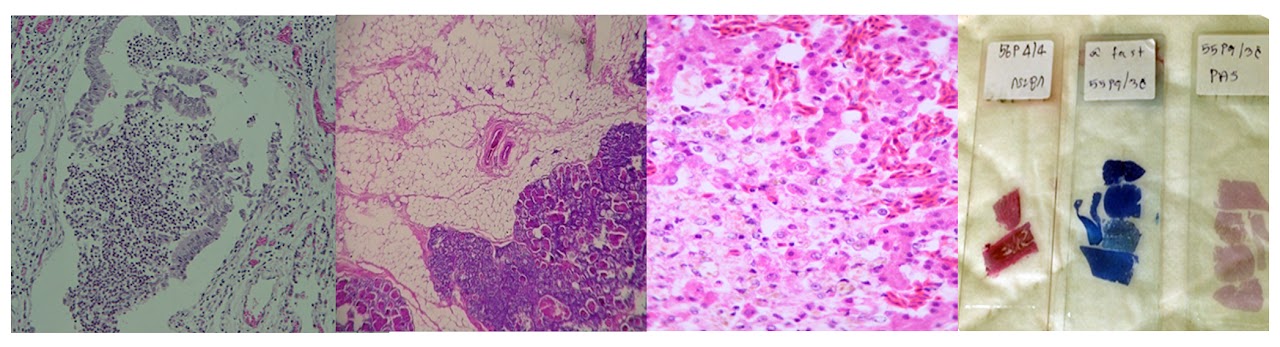

การตรวจหา Inclusion body ของเชื้อ Porcine Circovirus จากอวัยวะในระบบน้ําเหลืองสุกรโดยวิธีทางพยาธิวิทยา

ห้องปฏิบัติการผ่าซาก (necropsy)

ห้องปฏิบัติการจุลพยาธิวิทยา (necropsy)

ห้องปฏิบัติการอิมมูโนพยาธิวิทยา (Immunohistology)